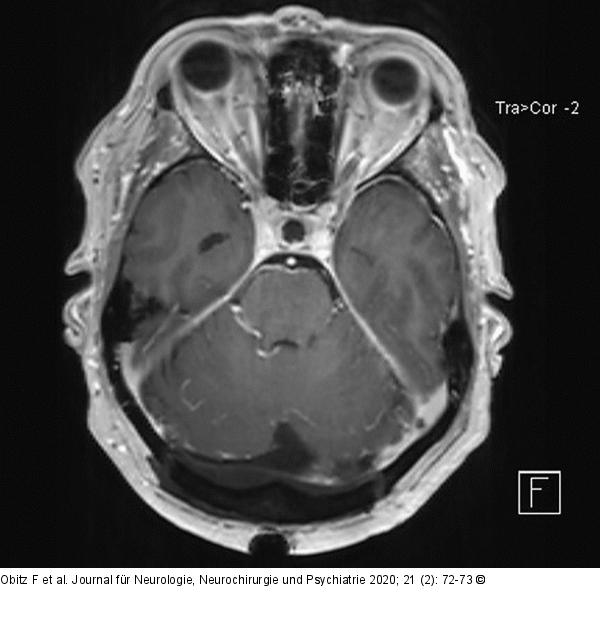

Abbildung 2: Okzipitalen Blutleiter Postoperatives cMRT axial, das weitestgehende Resektion der okzipitalen Blutleiter zeigt |

Abbildung 2: Okzipitalen Blutleiter

Postoperatives cMRT axial, das weitestgehende Resektion der okzipitalen Blutleiter zeigt |